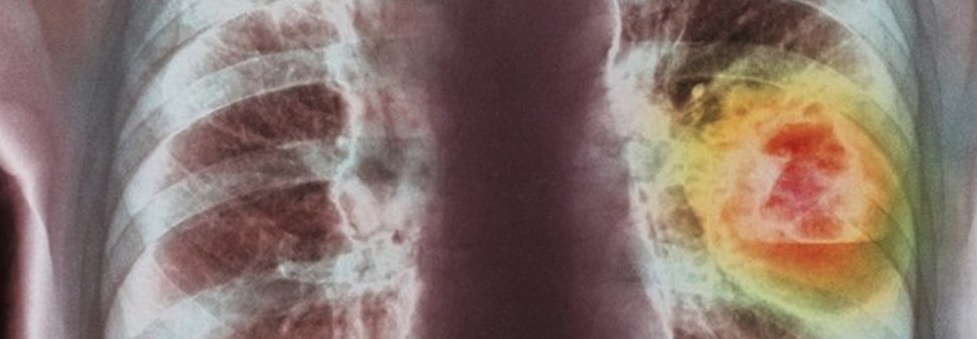

Мелкоклеточный рак легких (МРЛ) и немелкоклеточный рак легких (НМРЛ) различаются по нескольким ключевым характеристикам.

МРЛ обычно связан с курением и имеет более агрессивное течение, быстро растет и часто метастазирует на ранних стадиях.

Мелкоклеточный рак легких (МРЛ) считается одним из самых агрессивных видов рака. Пятилетняя выживаемость пациентов с МРЛ составляет примерно 6%, так как этот тип рака обычно диагностируется на более поздних стадиях и быстро метастазирует. Однако ранняя диагностика и лечение могут значительно улучшить прогноз.